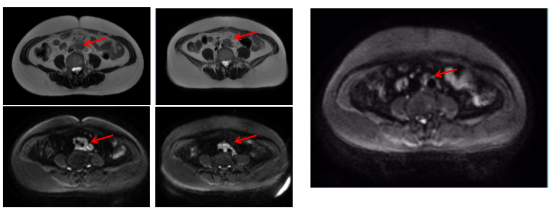

2019-03-18复查出现肺转移(术后17个月)(1)胸部增强CT:右肺上叶尖段占位:考虑恶性肿瘤,转移瘤?原发?(大小2.5*2.5cm)。(2)全腹部增强MRI示:乙状结肠癌根治术改变,吻合口区未见明显恶性征象;左侧前庭大腺囊肿增大,建议随访;盆底腹膜略增厚同前,盆腔微量积液;DWI上骨盆骨质弥漫信号增高同前。(3)全身骨显像:L4-5椎体血运丰富、代谢旺盛,多考虑良性病变;下颌骨左侧齿槽炎;颅骨骨质疏松改变。(4)CEA、CA19-9正常范围

image.png

图2 术后17个月复查的影像学结果